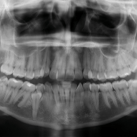

CONHEÇA NOSSA ROTINA CIRÚRGICA